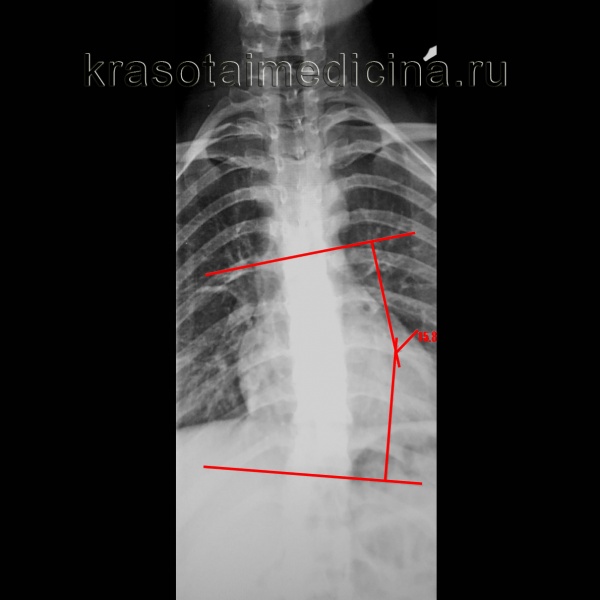

Рентгенография грудного отдела позвоночника. Левосторонний сколиоз 2-й ст. с углом дуги около 15,8 градусов (по Коббу), с центром на Th9.

о Стандартным методом количественной оценки величины сколиотической деформации является метод Кобба:

- Строятся две линии, соответствующие замыкательным пластинками терминальных позвонков

- Если четко дифференцировать замыкательные пластинки не удается, в качестве ориентиров используют корни дуг

- Угол Кобба - это угол между замыкательными пластинками двух терминальных позвонков

- Можно измерять угол между двумя перпендикулярами к замыкательным пластинкам терминальных позвонков

- Этот второй метод упрощает измерение при небольших искривлениях